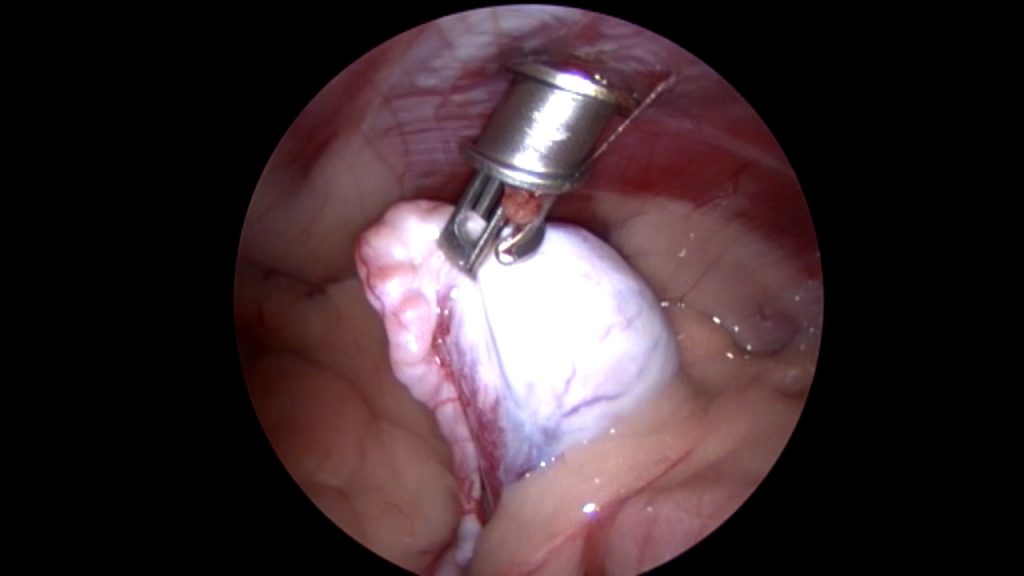

Op de operatietafel kunnen we vervolgens met behulp van de scoop de cryptorche testikel nauwkeurig lokaliseren en bepalen waar de bloedvaten zitten, die we niet willen raken. Vervolgens kan dan zeer gericht een 2e trocar (dit is een canule van bijvoorbeeld 5 mm breed, waardoor je vervolgens met een tang de buik in kunt) geplaatst worden om de testikel tegen de buikwand te halen en te kunnen verwijderen. Al met al heb je dan 2 veel kleinere gaatjes in vergelijking met een echte buikoperatie.